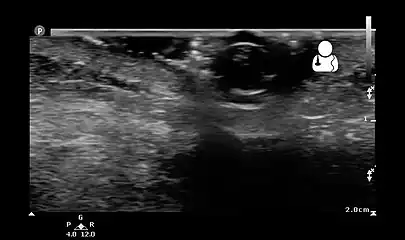

- Ultrasound showing maggot infestation[24]

- Ultrasound showing maggot infestation[24]

Ultrasound showing maggot infestation[24]

Ultrasound showing maggot infestation[24]